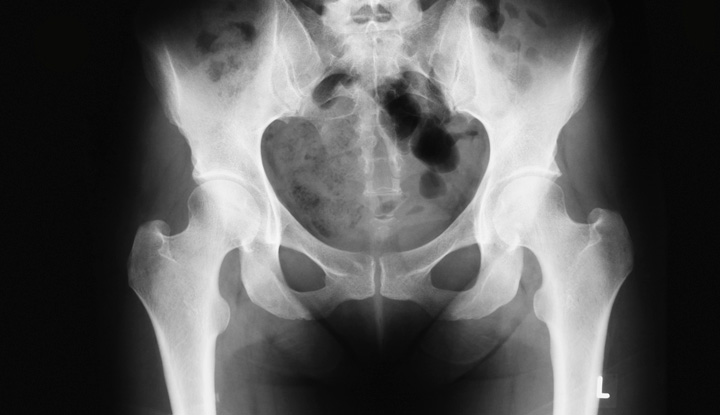

what are primary and secondary match structures on AP imaging?

primary: pubic symphysis or pelvic brim

secondary: obturator foramen or iliac crests

what rotational translation could be suggested with a mismatched obturator foramen?

A roll rotation: one hip is higher than the other

What structures are useful for assessing symmetry during global assessment?

Obturator foramen, pelvic inlet, iliac crests, femoral heads.

What indicates a roll error on a/p imaging

Pelvic inlet or obturator foramen not lining up; one hip higher than the other.